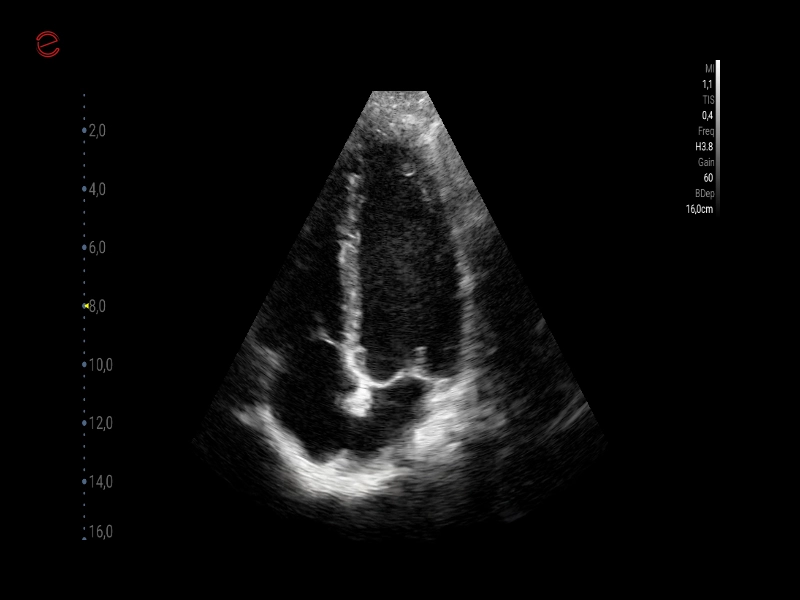

MyLab™C30 - Bmode - Plax

MyLab™C30 - Bmode - Plax

MyLab™C30 - Bmode - 3CH

MyLab™C30 - Bmode - 3CH